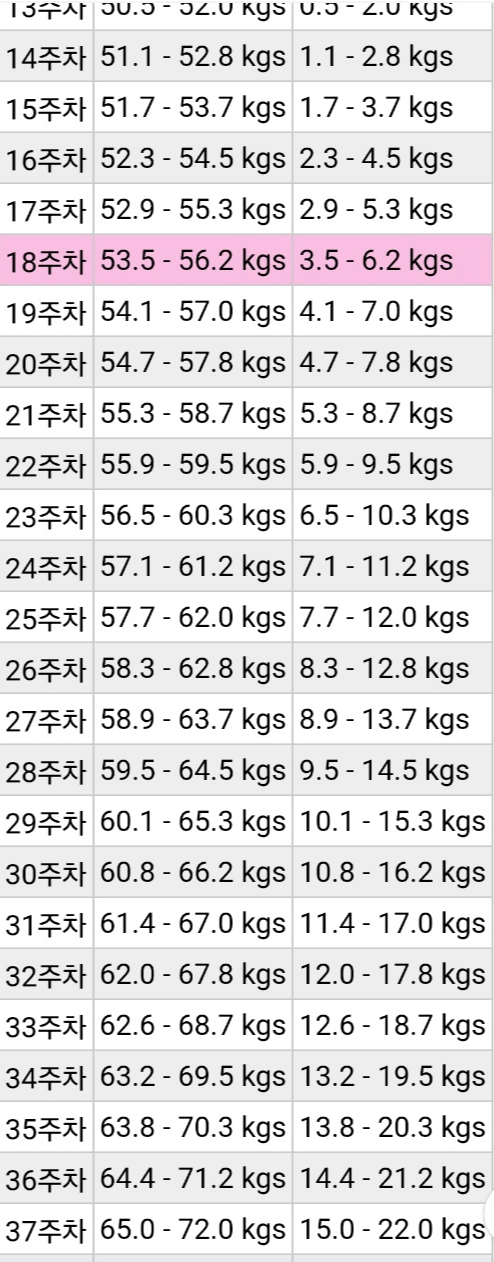

임신을 하면 아기들에게 영양분을 줘야 하기 때문에 대체로 많이들 찐다고 하는데 난 운이 좋게도 크게 관리한 거 없이

평소 먹는 대로 먹고 잤는데, 37주인 오늘 몸무게는 64.7kg 정도다. 임신 전이 49kg였으니 15.7kg 정도 찐 거 같다.

출산을 3일 앞두고 있으니 아마 16kg 정도 찌고 출산할 것 같다.

임신 후 적정 체중에 대해 궁금하면 아래 체중 증가 계산기 사이트를 통해 알아보는 걸 추천한다.